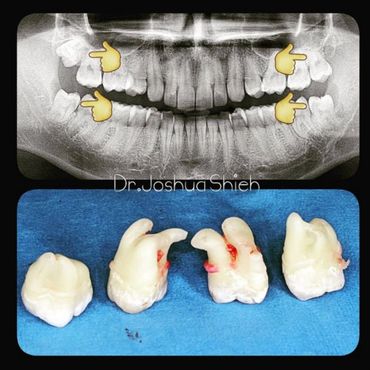

If the tooth is planned for extraction, an x-ray of the area will be taken to plan for the type of extraction.

Simple extractions are performed on erupted teeth that have regular anatomy (root and crown), and are not severely broken.

Early Wisdom Teeth Extraction

Wisdom teeth are the third set of human molars. Unfortunately, in some cases, those teeth are impacted fully or partially in bone or soft tissue and cannot erupt causing pain, discomfort and swelling. Additionally, most people have difficulty accessing these teeth during brushing or flossing causing accelerated decay and gum problems. Wisdom teeth have also been notorious for causing crowding, improper bites and pressure when they start erupting. The arrival of these late-breaking teeth can cause trouble as they are often impacted (trapped in the jawbone) because there is not enough room for them in the mouth. Our jaws are a lot smaller than those of our early human ancestors, who needed bigger jaws and more teeth for the type of food they chewed. In most people, wisdom teeth can do more harm than good and we often recommend their removal.

It can take a long time for wisdom teeth to erupt and you may not even notice the harmful effects in your mouth until you experience sudden and severe discomfort. Cramped for room, impacted wisdom teeth grow out at odd angles or remain trapped below the gums. Adjacent teeth can become prone to decay because of the unfavourable position of the wisdom teeth.

If you feel that your wisdom teeth are starting to cause problems, book an appointment to assess their condition, a panoramic x-ray will be taken and a thorough examination is conducted.